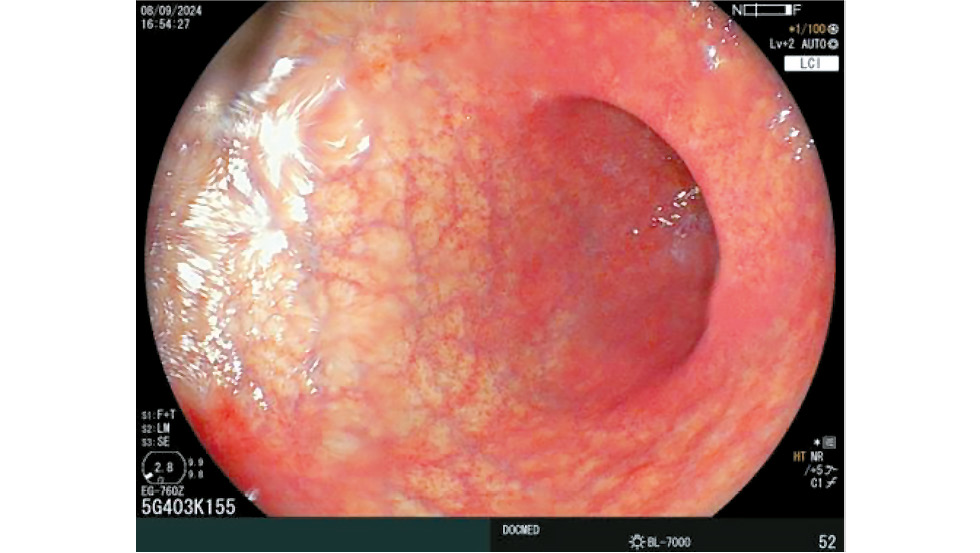

Esophagogastroduodenoscopy with biopsy is the primary method for diagnosing autoimmune gastritis. Reports from the late 19th and early 20th centuries described gastric body atrophy in patients with pernicious anemia. In 85% of these cases, atrophic changes were more pronounced in the gastric body (Fig. 1) [40].

Fig. 1. Diffuse atrophy of the gastric body mucosa when examined in inversion (a) and direct projection (b). © Eco-Vector, 2025.

However, according to Kishino et al., autoimmune gastritis was missed in 49% of cases during endoscopic examinations [12].

A well-known endoscopic feature of autoimmune gastritis is the reverse atrophy sign, which serves as a key indicator of the disease. In a multicenter study by Krasinskas et al., this sign was detected in 90.1% of patients in Japan [41]. Other endoscopic findings commonly observed in autoimmune gastritis are illustrated in Fig. 2.

Fig. 2. Endoscopic view of “reverse” atrophy. Atrophic changes mucosa of the body of the stomach with preserved mucosa of the antral section. © Eco-Vector, 2025.